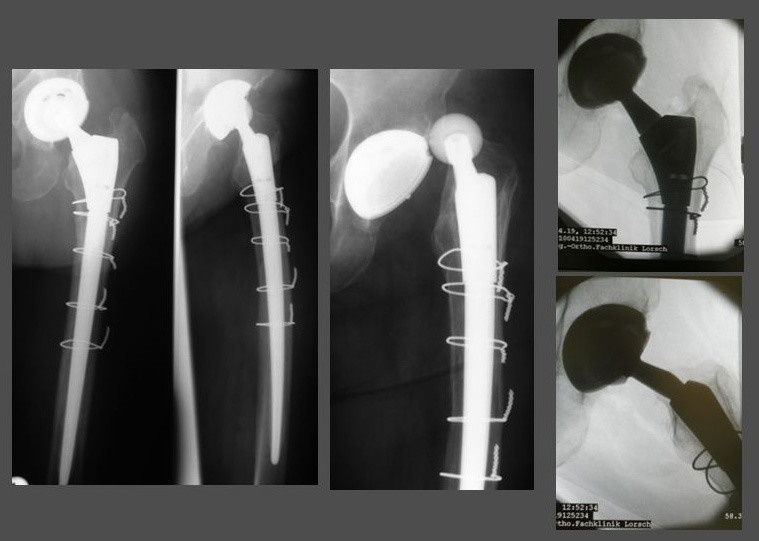

e. Anpassungsmöglichkeit an schwierige Defektsituationen und Knochenverluste.

Bei der großen Varianz an Defeksituationen, die einem im Rahmen von Revisionsoperationen begegnen, erlauben modulare Revisionskomponenten auch die Versorgung extrem ausgedehnter Knochendefekte (Abb. 5).